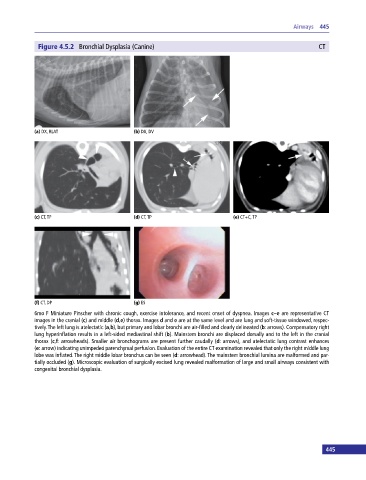

Figure 4.5.2 Bronchial Dysplasia (Canine) CT

6mo F Miniature Pinscher with chronic cough, exercise intolerance, and recent onset of dyspnea. Images c–e are representative CT

images in the cranial (c) and middle (d,e) thorax. Images d and e are at the same level and are lung and soft‐tissue windowed, respec

tively. The left lung is atelectatic (a,b), but primary and lobar bronchi are air‐filled and clearly delineated (b: arrows). Compensatory right

lung hyperinflation results in a left‐sided mediastinal shift (b). Mainstem bronchi are displaced dorsally and to the left in the cranial

thorax (c,f: arrowheads). Smaller air bronchograms are present further caudally (d: arrows), and atelectatic lung contrast enhances

(e: arrow) indicating unimpeded parenchymal perfusion. Evaluation of the entire CT examination revealed that only the right middle lung

lobe was inflated. The right middle lobar bronchus can be seen (d: arrowhead). The mainstem bronchial lumina are malformed and par

tially occluded (g). Microscopic evaluation of surgically excised lung revealed malformation of large and small airways consistent with

congenital bronchial dysplasia.